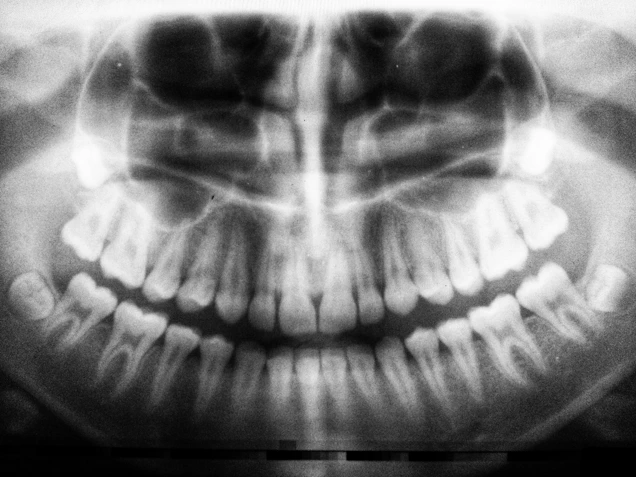

We evaluate wisdom teeth with X‑rays to understand their position and roots, explain the procedure, and provide clear instructions for post‑operative care and healing.

teeth X-ray